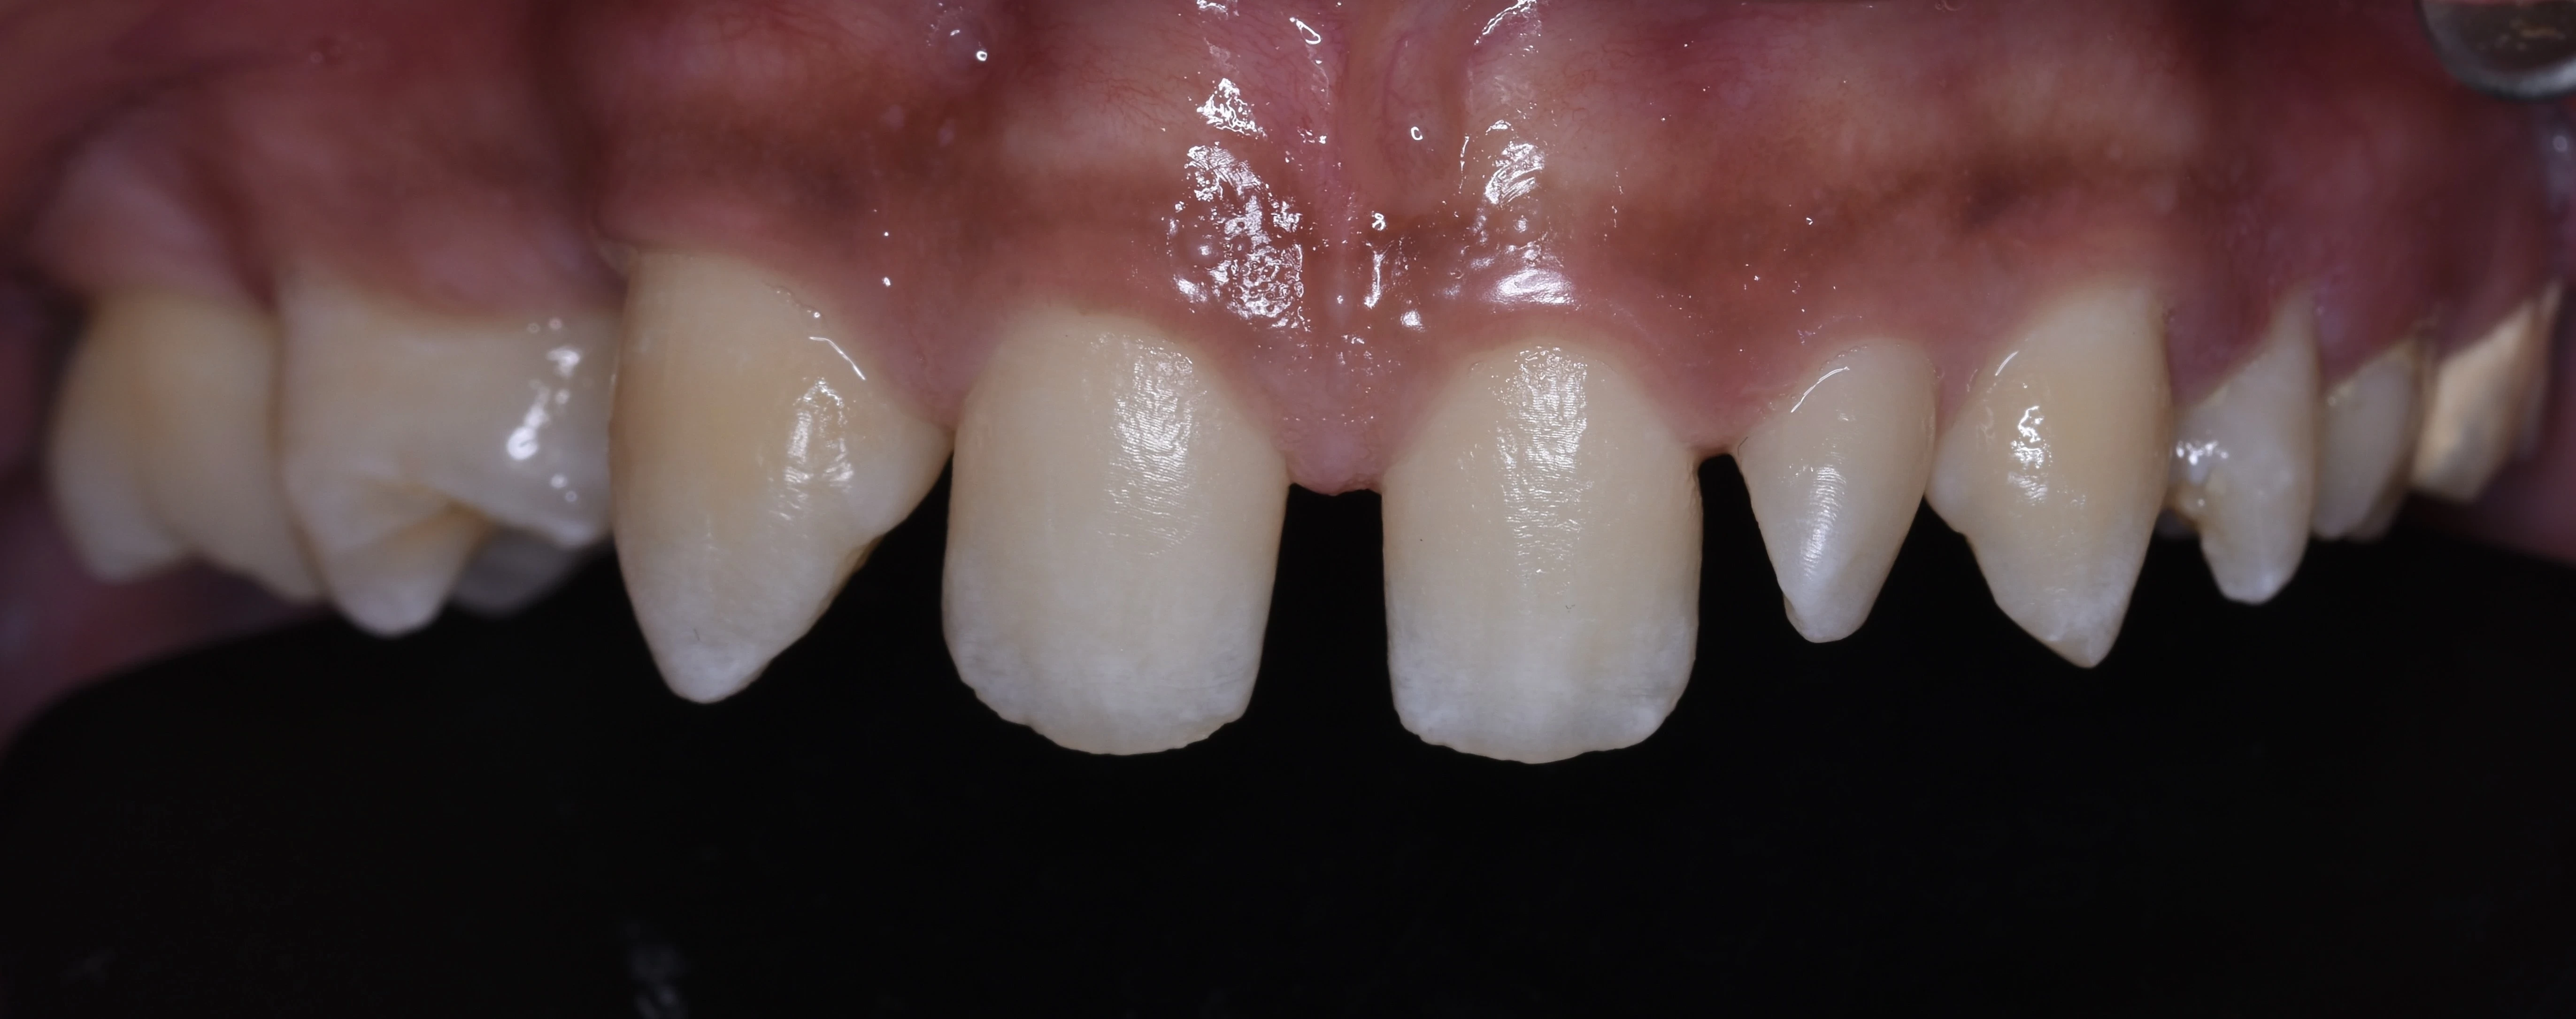

يلجأ الشخص إلى تحسين شكل أسنانه عن طريق فينير الأسنان أو ما يطلق عليه (عدسات الأسنان اللاصقة) وهي عبارة قشرة رقيقه يتم لصقها على السطح الخارجي للأسنان مصنوعة من مواد صلبة ذات معامل شفافيه مطابق للأسنان الطبيعيه   لعلاج مشكلة الاصفرار أو عدم التساوي والعديد من المشاكل الأخرى، حتى يحصل الشخص على ابتسامة رائعة تشبه ابتسامة نجوم هوليود.

•  تغير لون الأسنان الطبيعية من اللون الأبيض للون الأصفر.

• وجود مسافات بين الأسنان.

• تكسر وتشقق الأسنان.

• عدم تناسق الأسنان او اعوجاجها.

• وجود حشوات عديده بالأسنان الأماميه ذات مظهر سيء.